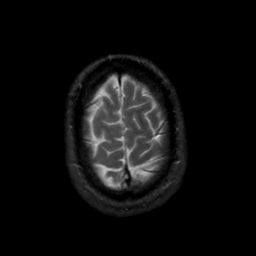

MR Study #18, July 21, 1991 -- Slice #44

[Home][Help][Clinical][Tour 1][Tour 2] Slice 44